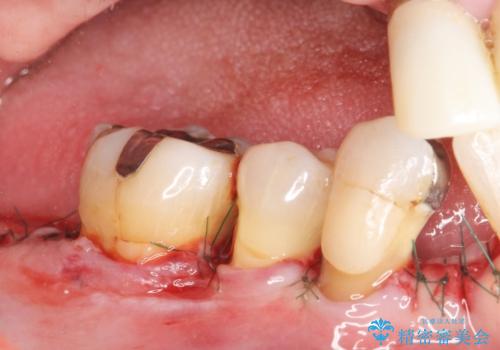

骨吸収の進行している右下臼歯部に、再生療法(骨を増やす手術))を行いました。

再生療法から1年後、リエントリー手術により骨の再生を確認し、骨外科処置(骨を平らにして歯周ポケットの根本的な改善を図る処置)を行いました。

埋伏していた親知らず、保存不可能な右下の一番奥の歯(右下7)、状態の悪い犬歯(右下3)は抜歯しております。